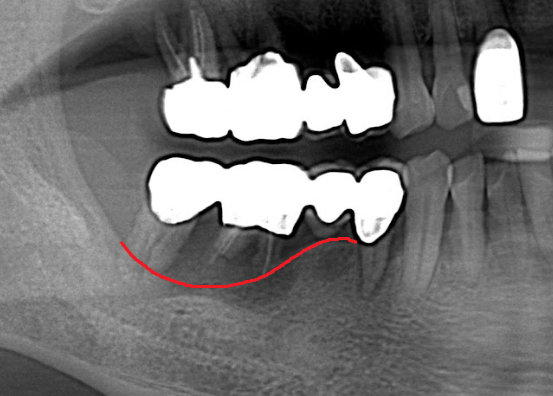

嚴重缺牙的後果? 不管是蛀牙導致的缺牙、退化所致的缺牙、意外造成的缺牙,嚴重缺牙最先會面臨到的問題是「營養流失」,長時間無法正常咀嚼、進食,吸收不佳的情況下,會導致營養不良。 此外,嚴重缺牙會讓口腔上下顎,無法對襯咬合,導致嘴巴無法正常閉合,除了影響美觀,長久下來,也會影響顳顎關節(temporomandibular joint)、咀嚼呼吸系統。 長時間缺後牙的後果? 「缺後牙沒有關係阿,反正看不到,用前面的牙齒咬就好」。這真的是大錯特錯的觀念,長時間缺後牙、錯失黃金治療期,後果,並非想像中的那麼簡單! 「上方後牙區缺牙」,會造成下顎後牙的牙齒往上移,導致錯位咬合,牙脊高度流失、上顎鼻竇腔膨大下墜。之後如果要植牙時,必須伴隨補骨、牙脊增高術或者上顎竇增高術。 「下方後牙區缺牙」,會造成上顎後牙的牙齒往下墜,導致錯位咬合,錯失黃金治療期,會讓牙脊高度、寬度流失,導致缺牙區沒有空間做假牙。 - 假牙的種類 2026.01.19

數位植牙的好處? 不管採取何種植牙治療方式,「4D微創導航系統」牙科技術能夠輔助醫師,在治療時,除了能透過醫師臨床的經驗與技術外,更能精準的控制與判斷病患的所有狀況,降低療程時可能發生的風險,以及減緩術後的不適感。 醫師會在病人的缺牙上,裝上一顆如同「監視器」的機器,搭配「4D動態導航系統」牙科技術,讓醫師在植牙的時候,能夠即時、精準的監測病人口腔骨頭內的狀況。 植牙有黃金治療時間嗎? 植牙的黃金治療期是「越來越快好!」為什麼是「越快越好呢?」最主要是因為牙齒與牙槽骨是相互依存的關係,當缺牙的第一年,骨頭會吸收得特別快,接下來每年以等比的速度吸收。 當口腔內的牙齒,有任何問題或是已經出現缺牙的情況,應該盡快尋求牙醫師的協助!進行治療與骨頭重建的需求評估,已避免增加重建的困難度,甚至無法治療。 到底適合「植牙」,還是要做利用兩邊牙齒做「牙橋」,最終還是需要經過醫師的專業判斷。 如何在茫茫醫海中,尋找適合的植牙醫師? 「一般牙科、贋復補綴科、口腔顎面外科、牙周專科」現代人很喜歡上網做功課,但想要找植牙醫師時,卻不知道從何尋找到適合的植牙醫師。 其實,能夠提供患者專業植牙技術的醫師,通常會受過「贋復補綴科、口腔顎面外科、牙周病科」這3大科的專業訓練。 擔心花錢後植牙出現問題又無法處理,如果長期看診的牙醫診所沒有相關的專業醫師,可以請醫師幫忙轉介。 另外,也可以挑選幾位自己喜歡的醫師,進行面診諮詢,找出最適合的醫師。最後,與醫師充分的溝通、配合也是植牙成功與否的重要關鍵。 植牙的步驟 植牙的流程大致可以分為幾個階段:資料蒐集、資料分析與重建理想牙位、植牙手術與植牙臨時假牙製作,以及最後最重要的植牙假牙製作。 植牙諮詢的第一步「資料蒐集」 資料蒐集、分析: 先利用口腔掃描機、臉部掃描儀、X光片、斷層掃描等,蒐集病患口腔整體環境、牙齦、骨頭的臨床資訊,以及紀錄顳顎關節與咬合的情況。 植牙手術 植牙手術:在經過專業的醫療團隊,進行術前評估後,以及擬定個人化的治療方針後,就會進入植牙手術的步驟,手術的步驟,會先進行牙齦翻瓣、鑽孔、植入人工牙根、縫合、拆線等。 不少人聽到上述步驟,或許已經頭皮發麻,專業的醫療團隊在治療的過程中,會搭配「舒眠麻醉」治療,能夠降低病患在過程中的不適感與恐聚感。 而通常人工牙根的癒合期大約需要6-12週的癒合,待癒合後才會進入「植牙臨時假牙製作」的製作。 植牙永久有效? 植牙有保固期 ? 「植牙成功後,就一勞永逸了嗎?就不用與醫師相見了嗎?」植牙它是鈦金屬釘子,植入骨頭癒合後,它不會蛀牙。但是,植牙周圍的牙肉跟骨頭,如果不妥善保養的話,還是會導致牙周病的發生,就是所謂的植體周圍炎。 植牙上方接出的牙冠,就好比買一台車,牙冠用久了,就如同車子用久了,零件、螺絲依舊會出現損毀的狀況,所以定期的回診保養追蹤是相當重要的。 通常植牙牙套完成後,至少半年回診一次,讓牙醫師檢查確認植牙附近牙齒沒有累積牙箘斑牙結石、植體周圍牙肉沒有發炎化膿,中間固定的螺絲沒有鬆動、牙套沒有破損、咬合狀況穩定等。 此外,患者必須維持良好的口腔清潔,可以參照之前我介紹的牙齒清潔方式,來保持好的口腔衛生、少抽菸等,如此搭配定期的回診檢查,可延長植體壽命。 植體的構造 植牙的治療過程很漫長,很多病患最常問的是「嘴巴內裝上的到底是什麼東西?」 今天的「植牙芯教室」就要帶你來認識「植牙整體的構造」(Dental implant) 口腔內的植牙由上→下依序是:牙冠、支台體、植體。 牙冠:又稱假牙冠、牙套,它是提供如同真牙的咀嚼功能,並且恢復美觀,永久性的牙冠最常見的材質為:全瓷、金屬合金、瓷熔合金屬。 支台齒:連接牙冠與植體的延伸部分,在中間點扮演重要角色,因為它必須要支撐牙冠的咬力,同時又要提供牙肉健康的生長環境,所以專科醫師在安裝時,必須依造病患口腔的狀況「客製化」的設計,ˊ尋找最適合的形狀、大小與角度。 植體:置入於缺牙的牙槽骨中,功能是取代原有的「牙根」,負責穩固牙齒的地基,目前最常見的植體材質為純鈦、鈦合金。 植牙x牙冠材質 對於越來越講求美觀的現代人來說,花錢植牙,當然希望它能美觀性與功能性兼具。 今天的「植牙芯教室」就要帶你來認識「牙冠材質」 目前,市面上永久性的牙冠最常見的材質為全瓷、金屬合金、瓷融合金屬 。 1.全瓷牙冠:材料有氧化鋯、強化玻璃瓷,不需要使用金屬,材質與人體的生物相容性高,同時具備高硬度的特性、高耐磨、耐高溫。在外觀上,呈色自然如同真牙,美觀性極佳。 2.瓷融合金屬牙冠:由於合金的成分複雜,若是高貴金屬的成分(黃金、白金)不夠高時,在口腔高溫潮溼的環境下,金屬容易腐蝕,導致表面粗糙,使牙菌斑難以徹底清潔,就容易造成牙齦發炎,並且染色,長期在美觀上、實用性都難以符合,對於外觀講求自然的病患。 3.金屬合金牙冠:由於整體採用金屬製作,所以不容易破裂、折斷,但是外觀呈現金屬色,所以當張開口時,便能夠一眼看出假牙的位置,如果使用金屬和金的牙冠,建議使用高貴金屬成分較高的材質。 植牙前的注意事項 想要提高植牙治療成功率,醫師與病患互相配合很重要,從術前的資料蒐集、評估與診斷,依據病人的情況,給予專屬的治療方針,從術中的治療過程,到術後的維護都非常重要,先來談談植牙前要注意那些事情。 1.保持口腔衛生:口腔清潔是植牙成功的最大關鍵 2.降低煙癮:抽菸會影響植牙的成功率,應該要盡量避免,如果能夠戒菸成功,更能提高植牙的成功率。 3.持續服用慢性病藥物:如果有在服用慢性病(高血壓、糖尿病等),在術前的諮詢,務必完整提供用藥歷史給醫師。 植牙後的潔牙步驟-工具篇 「植牙疏於潔牙與保健,百萬台幣立刻船過水無痕。」這是血淋淋的案例,真的不要以為,植牙完成後就一勞永逸。 術後的口腔清潔與維護非常重要!非常重要!非常重要!因為植牙的「使用壽命」,有非常大的關聯性。 植牙維護有三寶:牙刷、牙間刷、牙線 牙刷:可以選擇自己習慣的刷頭,或者選擇刷頭短小、刷毛軟硬適中的牙刷 牙間刷:當牙齦萎縮、牙縫變大時,應該選擇適合牙縫大小的牙間刷,用來清潔齒間的縫隙、牙套底層的牙菌斑與食物殘渣。 牙線:使用超級牙線,來清潔牙橋下的支柱牙部分。 漱口水、沖牙機等,這些只是輔助工具,千萬不能把它當作正規的潔牙器材。 植牙後的潔牙步驟-清潔篇 植牙的清潔方式。 首先:使用牙刷在假牙與牙肉的交界,採用刷牙法,來回輕刷至少10次。 接著:使用牙間刷,輕貼牙齒的表面,進行前後清洗,按照同一個方式,從舌側進入,輕貼牙齒表面,再做一次清潔,每次動作至少5次。 最後:使用大約45CM的牙線,可以使用穿引器的輔助,深入牙橋底下做清潔,每次動作至少5次。 植牙後的潔牙步驟-電動牙刷VS.一般牙刷 「做完牙套後可以用電動牙刷刷牙嗎?潔牙工具怎麼選?」上一篇,談了植牙的清潔方式,究竟植牙到底該不該用電動牙刷?答案是「可以」。 科學研究指出,使用電動牙刷,能更深入清潔到牙縫與牙齒倒凹處,尤其對於手部協調性沒那麼高的人,以及牙齒排列凌亂者,在清潔上能夠達到更好的效果。 刷頭的選擇:一樣要以刷頭小、刷毛軟硬度適中的刷頭,建議每1-3個月,或者外觀出現彎曲變形,刷頭就必須更換。千萬不要因為刷頭,比一般牙刷貴捨不得更換,反而會讓潔牙效果打折扣。 潔牙方式:電動牙刷與一般牙刷的潔牙方式的差異在於,電動牙刷只需要將刷頭輕放在單顆牙齒上,讓刷頭在牙齒與牙肉的交界處轉動,手不需要來回移動刷頭。但是千萬不要重壓,施壓過多的力道在牙齒上,反而對於牙齦是種傷害。 另外,不管使用電動牙刷或一般牙刷,都一定要使用牙線、牙間刷,來清潔牙齒與牙齒間的鄰接面,確保牙菌斑被清除。 潔牙時間:三餐飯後,30分鐘內如果能夠潔牙是最好的,如果無法達到,睡前徹底的潔牙是最重要!另外,潔牙時一定要有耐性,不要為了節省時間,隨便刷2.3下就結束。 如何選擇:預算、操作與攜帶方便度為首要考量,而且選擇具有「經濟部標準檢驗局」檢驗合格的產品,設計不良的電動牙刷,可能會造成口腔受傷。 植牙後的術後照護 植牙的最終成功與否,術後照顧真的非常重要!務必遵從醫囑,以下是照護的重點。 1.冰敷:術後1周,依舊會有些許的腫脹與輕微的瘀青,在48小時內,建議患者可以冰敷,在臉頰外側冰敷15-20分鐘,休息10分鐘,重覆動作到48小時。 2.不要泡溫泉、熱水澡,以及從事游泳與劇烈的運動。 3.飲食方面:初期還是會建議以流質、軟度高的食物為主,過燙、過冰的流質食物則不宜,應該避免食用過燙、辛辣、含有酒精成分刺激性的食物。 4.降低菸癮:為了讓植牙的傷口能順利恢復,醫學上皆有文獻記載,術後1周必須降低菸癮。 5.定期回診:植牙完成還是必須定期回診,讓醫師確認傷口、口腔健康的情形。 根據手術療程的不同,每一項術後的照護方式也有所差異,未來會跟大家分享與討論。 植牙後就能一勞永逸,不會有牙周病? 大多數的病患都知道,植牙前要先把牙周病及其他口內問題處理好,以降低口內細菌數量,才能夠進行植牙,但是很多病患以為,植牙成功,同時也能跟牙周病永久說再見,這觀念完全不正確。 簡單說「牙周病」是牙齒的周圍骨頭受到細菌的破壞,所造成的結果。因此,在植牙後,如果植體周遭的牙肉與骨頭,沒有得到妥善的清潔與照顧,還是會造成口腔內細菌的滋生,一樣會導致牙周病的發生。 植牙後,是不是也跟敏感性牙齒Say Bye Bye 一般所說的「敏感性牙齒」真正的學名是「牙本質知覺敏感症(Dentin Hypersensitivity)」會造成敏感性牙齒,主要原因是在於牙齒外層的琺瑯質被磨耗後,失去保護的功能; 或是牙齦萎縮牙根裸露時,都會造成牙本質內的神經小管暴露,當受到冷熱、吹氣、和壓力等刺激下,所產生的神經疼痛不適感。 植牙後,重建的人工牙冠內沒有神經,所以不會有敏感性牙齒的發生。然而,其他的自然牙齒,不會因為植牙而受到改變,當琺瑯質被破壞時,依舊會造成牙齒敏感性的問題。 骨質疏鬆的人適合植牙嗎? 「骨質疏鬆」有越來越年輕化的趨勢,除了因為年齡的增長之外,身體未獲得適當的保養也是元兇之一。如果是輕微的骨質疏鬆,只要適當的補充鈣質,想要植牙依舊沒有問題!整體還是必須交由專業醫師評估。 「骨鬆患者」,尤其是有在服用高劑量或施打抗蝕骨作用的藥物,是會影響植牙的成功率。原因在於,大多數的抗骨質疏鬆藥物,含有雙磷酸鹽,會影響骨骼細胞修補的功能,讓顎骨無法修復。所以如果有服用相關藥物,植牙前一定要告知醫師。 我是高血壓患者,能夠植牙嗎? 在高血壓控制好的前提下,是可以進行植牙手術的!正常的血壓是指收縮壓120/舒張壓80mmHg,當血壓偏高時,會增加手術中的出血狀況,提升手術的複雜度,甚至會提高手術後的感染率。 很多高血壓患者會服用「抗凝血藥物」。「抗凝血藥物」可能會在手術時,出現傷口流血不止的問題,所以醫師在進行植牙評估時,一定要讓醫師了解自身的慢性病史與用藥,並且盡可能尋找能提供詳細治療計畫,以及擅長微創植牙手術的醫師,降低植牙的風險。 我是糖尿病患者,能夠植牙嗎? 糖尿病患者與高血壓患者,都是在控制良好的前提下,能夠完成植牙手術。由於糖尿病控制不良的患者,細胞修復的能力與免疫系統,跟正常人比起來比較低,相對的牙周組織再生能力、傷口癒合情況也比較差。 所以想要植牙,必須同時與新陳代謝科醫師與植牙醫師相互合作,穩定血糖。除此之外,糖尿病患者也應該養成良好的口腔保健習慣,在經過醫師的專業評估,提供完善的治療計畫。 糖尿病與牙周病的關係? 「牙周病已經被列為糖尿病的併發症之一」前面談到「只要控制好血糖」依舊能夠植牙。我們也提到植牙前,一定要把牙周病控制住。今天我們就來談談「牙周病與糖尿病控制不良的關係」。 事實上,糖尿控制不良的病患發生牙周病的機率是正常人的3倍。最主要的原因,口腔細菌量會比正常人多,由於免疫系統比較差,更容易受到感染,所以傷口的復原能力也較低。 一旦糖尿病控制不良者得到牙周病時,病程也會跟著加速,骨頭被破壞與受損的速度也會加快。並且,因為身體長期發炎,將會導致血糖更不易控制。 癌症患者適合植牙嗎? 「癌症已經連續多年佔據國人10死因的首位」而癌症到底能不能進行植牙手術呢?首先,醫師會先了解病人的癌症種類與期數,以及過去的病史、治療史、用藥史,經由病人提供的資料,來做精準的判斷。 癌症的放射治療、免疫抑制等是會影響到傷口的癒合,治療上會使用到,抗骨吸收藥物 (antiresorptive agents)與抗血管生成藥物(antiangiogenic agent)等,都很有可能增加顎骨壞死的風險。另外,頭頸部經過放射線照射後,也會造成骨細胞的活性降低。 而且病人在接受化療、標靶藥物時,也會因為治療後,免疫力降低,細胞修復能力變弱,如果在治療期間,或是在治療後,想要做植牙,都應該先找醫師進行評估身體各項數值,以提高植牙成功率。 懷孕期間能夠植牙嗎? 雖然植牙是一個小手術,但是通常醫師都不會建議準媽咪們,在這時候進行植牙手術,首先,因為植牙是必須照X光檢查,在懷孕期間,應盡量避免暴露在輻射線下。 同時植牙必須經過麻醉的步驟,雖然麻藥會經由尿液排除體外,但大多數麻藥都含有「血管收縮劑」的成分,在治療過程中引發的加倍焦慮,可能會造成者子宮提前收縮的風險。所以會建議想植牙的準媽咪,產後再進行植牙手術。 產後、哺乳期植牙注意事項 「醫師,我正在哺乳期能植牙嗎?」在懷孕期間,就算已經完成第一階段的植牙手術,醫師為了保護母體與胎兒,會直接將療程暫停至產後,但是女性「產後要多久才能植牙?」、「哺乳期能植牙嗎?」成為許多媽媽最常問的問題。 事實上,女性產後的身體狀況恢復到一定的程度,就能夠進行植牙。而為了擔心麻醉藥或是抗生素、止痛藥分泌到母乳,加上每種藥物的半衰期不同,通常會建議,服用完最後一次藥物,在相隔24小時後,才進行哺乳。 服用健康食品是否會影響植牙 「維他命C、B群、魚油、銀杏、補鈣產品...」各式各樣的保健食品有吃有安心,很多病患到了診間,最常問我的問題之一「醫師,我有在服用各類的保健食品,會影響植牙嗎?」 事實上,需要看服用保健食品萃取的成分而定,不是所有的保養品食品,都會影響植牙的。如果營養品中含有「抗凝血作用」成分的保健食品,例如:銀杏、紅花。會建議在術前1周暫停服用。 雖然,適當的服用保健食品,確實有益於健康,但是在進行植牙評估時,還是務必告知,讓醫師做更正確的評估。 植牙要局部麻醉還是全身麻醉? 「植牙到底要全身麻醉,還是局部麻醉?麻醉的方式有哪些?差異性、有沒有後遺症?」許多病患都會有相同的疑問,從今天開始,一連串的文章來解惑。 其實,植牙手術跟一般口腔治療的方式一樣,能夠在病患清醒情況下進行治療,醫師通常會使用局部麻醉藥內含少比例血管收縮劑(Epinephrine),針對病人的手術內容,與治療所需的時間,給予準確的麻醉劑量。 由於大部分的局部麻醉藥,含有血管收縮劑,之前文章有提到高血壓的患者,必須在做治療諮詢時,提供用藥史與血壓控制情形,並且在手術當天,都應該接受血壓的測量,已確定用藥的安全性。 植牙的成功率?植牙失敗怎麼解?植牙的後遺症? 「植牙能100%成功嗎?植牙後是不是就再也不用回診?當植牙開始出現問題時,怎麼辦?植牙失敗後該如何治療?」這些問題是現在病患在選擇植牙時,很重要的考量。 「植牙成功率及植體壽命的長短」其實,最重要的是取決於醫師、病患有沒有合作無間,醫師與病患都應該在治療的過程中,扮演好彼此的角色,才能在植體成功骨整合後,延長使用的壽命。 病人,在諮詢時,要確實的將藥物史、病史提供給醫師。在治療期間,遵照醫囑、落實口腔衛生,並且在術後定期回診。此外,當植體出現任何情況時,必須立刻尋求醫師的協助「及早發現、及早治療」。 醫師,在技術、經驗上必須給予病患精準個人化的治療方針,並且選用大品牌的植體、生物醫材,提高治療成功率。同時,隨時吸收醫療新知,並將它運用,讓病患得到最好的治療。 上述都是植牙成功不可或缺的關鍵之一。 植牙後出狀況x牙冠瓷破裂 「植牙後出狀況怎麼辦?」 就如同之前所說,植牙就像是一部車子,用久了零件會出現受損的情況,要聊「出狀況怎麼辦?」就要回歸問題的根源來對症下藥,接下來,我將針對「植牙後常見的幾大狀況」來做詳細的說明: 牙冠瓷破裂:可將假牙取下,送修補瓷以回復美觀及咬合功能。因為牙科材料學的進步,新式二氧化鋯牙冠 (Zirconia),幾乎不會有破裂的狀況,這也是目前牙冠材質中,在品質與美觀上的表現,都擁有較高的穩定性。專業的贋復醫師在修復之前,會先把連接體跟牙冠中間的隙縫清潔乾淨,讓植體免於細菌感染的風險。 植牙後出狀況x植體配件的鬆脫、受損 「植體配件的鬆脫、受損」,之前的植牙芯教室,我們有介紹,牙冠與支台齒內含有各種不同的小零件,當植體用久了,零件開始出現狀況,該如何處理? 要談到該如何處置之前,要先了解,為什麼會發生「植體配件的鬆脫、受損」的狀況,大致可以把原因歸類為:零件壽命、植體長期咬合受力。 病患完成植牙後,在每半年的定期回診,牙醫師都會針對這些細部零件做確認,確定是否有鬆脫或晃動的情形出現。 一旦出現螺絲的鬆脫情況,沒有及時治療,螺絲就會斷裂在植體內,而要從植體內,將斷裂的螺絲取出,是件複雜又具高風險的療程,必須由經過專業訓練的植牙贋復科醫師來做處置,在往後的文章,將再做更詳細的說明。 植牙的麻醉方式有哪些? 「舒眠麻醉、全身麻醉、笑氣麻醉」這是目前大家在搜尋資料時,比較容尋找到的關鍵字,今天就來簡單介紹,這些麻醉的專有名詞。 舒眠麻醉:目前贋復科醫師最常使用的麻醉方式,屬於淺層麻醉,能夠讓病患在放鬆的情況下進行治療,也能夠降低局部麻醉的用藥量,關於「舒眠麻醉」接下來會一系列的介紹。 全身麻醉:屬於深度麻醉,麻醉藥的劑量會讓病患意識消失,而且無法自主呼吸,術後的恢復期較長,必須要在開刀房內進行。 笑氣麻醉:主要是用來鎮靜,而非麻醉,有些病患在做口內局部麻醉時,依舊會感受到看牙的緊張感,因此,有些醫院或診所,會備有笑氣設備,幫助病患在局部麻醉時,能夠鎮定。 植牙的評估要件懶人包 Q:缺牙會影響到那些層面? A:身體、心理都會受到影響,長期缺牙會讓導致「咬合障礙」 Q:到底要植牙,還是要做假牙? A:需要經過醫師的專業評估與判斷,「假牙」與「植牙」各有優、缺點。 Q:幾歲適合植牙? A:只要經過牙醫師臨床的評估,不管是25歲較年輕的缺牙病患,或者80歲的族群都能。 Q:如何在茫茫醫海中,尋找適合的植牙醫師? A:專業植牙技術的醫師通常會受過「贋復補綴科、口腔顎面外科、牙周病科」3大科的專業訓練。 Q:怕痛的人,如何進行植牙手術? A:現在也出現了「舒眠治療」,讓患者在治療上,大幅減低焦慮感。 Q:我是高血壓患者能植牙嗎? A:在高血壓控制好的前提下,是可以進行植牙手術的! Q:骨質疏鬆的人適合植牙嗎? A:如果是輕微的骨質疏鬆,只要適當的補充鈣質,想要植牙依舊沒有問題。 Q:癌症患者適合植牙嗎? A:在癌症治療期間或是在治療後,想要做植牙,都應該先找醫師進行評估身體各項數值,以提高植牙成功率。 Q:懷孕期間能夠植牙嗎? A:植牙必須經過麻醉的步驟,所以想植牙的準媽咪,產後再進行植牙手術。 Q:服用健康食品是否會影響植牙? A:需要看服用保健食品萃取的成分而定,不是所有的保養品食品,都會影響植牙的 舒眠治療懶人包 Q:舒眠治療有健保給付嗎? A:舒眠自療跟植牙如同屬於自費項目,並無健保給付。 Q:舒眠治療前需要做哪一些準備? A:由於治療藥物的濃度,與個人身體狀況與病史有關,所以患者必須確實告訴醫師用藥的習慣以及病史,必要時,在舒眠治療前,醫師會要求病患,先做身體健康檢查。 Q:平常有習慣吃保健食品需要暫停嗎? A:大部分的保健食品都不需要停藥。 Q:舒眠治療需要禁食嗎? A:需要的,必須至少禁食6-8小時,如果是在上午進行,前晚12時之後就不可飲食,如果是下午,則是早餐過後,就不能進食。 Q:舒眠治療前的禁食,若有需要服用藥物該怎麼辦? A:禁食期間,服用少量的水吃藥是被允許的。 Q:有服用抗凝血藥物怎麼辦? A:通常不需要停藥,除非是經過專業醫師指示,才需要停藥。 Q:舒眠治療當天可以駕駛嗎? A:舒眠完成後,可能會有頭暈的狀況出現,建議在親朋好友陪同下,搭乘交通工具前往診所。 Q:舒眠治療後的注意事項? A:在完成治療後,患者應休息20-30分鐘,確保沒有暈眩、嗜睡的情況發生,才能離開診所。 植體品牌 ║史得勞曼(Straumann)║ 瑞士的植牙品牌,經過許多臨床醫學研究證實,是植體品牌中邊緣骨流失最少的系統之一,其特殊植體連接體的設計,使牙冠與植體緊密結合,增加假牙的穩定度,降低鬆脫、晃動的機率。 →https://reurl.cc/8lDo1X ║諾保科(Nobel biocare)║ 瑞典的植牙品牌,在2008年推出的NobelActive系統,植體特殊的螺紋設計及表面處理,適用於骨質條件狀況比較複雜的患者。 →https://reurl.cc/xDN9zL ║亞仕特(Astra Tech Implant)║ 瑞典的植牙品牌,在植體與連結面的設計上,採用特殊的圓錐六角形內接式的設計,穩定的接口,能降低牙冠與支台齒,鬆脫的情形。 →https://reurl.cc/jd91bn ║百好(BIOHORIZONS)║ 來自美國的植體品牌,BioHorizons採用硬度、生物性較高的鈦合金材質,同時擁有特殊的Laser-lok專利技術,不僅能降低植體牙周病的發生機率,又達到兼顧美觀的功能。 →https://reurl.cc/YlYvZn ║貝格莎曼杜(BEGO Semados)║ 德國在地生根、製造生產超過125年的歷史悠久,植體表面特殊的TiPure技術,能夠幫助植體與齒槽骨結合,達到最大的整合功能,同時,也能幫助植體壽命的延長。 →https://reurl.cc/oD81ov” - 植牙後的保養 2026.01.19